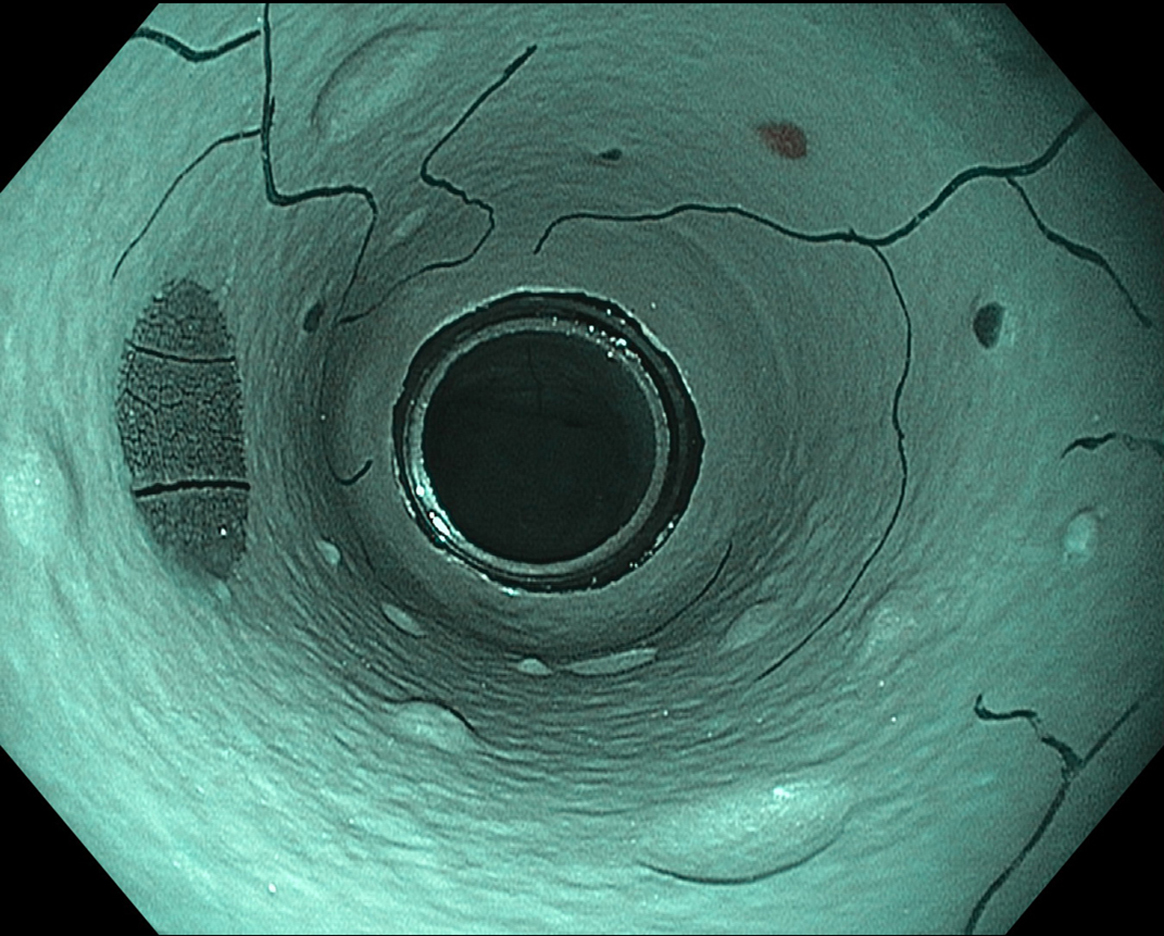

EVIS LUCERA ELITE × GIF1200N 症例画像

遠景部分において明るい視野が確保できる(血管の例)

EVIS LUCERA ELITE×GIF-1200N